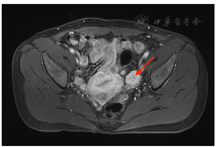

辅助检查:LH 1.7 IU/L(正常参考范围7.7~58.5,下同)、FSH 4.1 IU/L(25.8~134.8)、催乳素544.0 mIU/L(131~647)、雌二醇137.0 pmol/L(<505)、孕激素0.9 nmol/L(<0.401)、睾酮(T)6.4 nmol/L(0.101~1.42)、硫酸脱氢表雄酮(DHEAS) 6.27 μmol/L(0.101~1.42)、质谱法T 4.713 ng/mL(0.02~0.45)、质谱法DHEAS 4.3 ng/mL(4.30~6)、质谱法雄烯二酮1.218 ng/mL(0.2~0.75);餐后2 h血糖9.5 mmol/L(<7.8)、餐后2 h胰岛素97.4 μU/mL、餐后2 h C肽12.5 ng/mL;三酰甘油1.95 mmol/L(<1.7);红细胞5.52×1012/L(3.8~5.10)、血红蛋白182 g/L(115~150);余尿粪常规、肝肾功能、电解质、离子浓度、出凝血、空腹血糖、糖化血红蛋白、骨密度、肿瘤标志物、甲状腺激素、生长激素、肾素-血管紧张素-醛固酮、肾上腺素、去甲肾上腺素、促肾上腺皮质激素及皮质醇昼夜节律等未见明显异常。骨密度提示骨质疏松(腰椎T-1.9、髋关节股骨颈T-2.5);经阴道及腹部超声及盆腔增强MRI均提示子宫多发肌瘤、左侧附件区实质占位,大小约2.8 cm×1.9 cm(图1);肾上腺增强CT提示左侧肾上腺小结节,大小约1.1 cm×0.9 cm,腺瘤机会大(图2)。